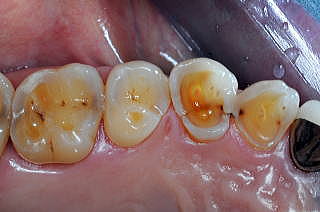

■症例2:酸食症 Acid Erosion

患者:73歳、女性。

咬合面Enamel質はすべて溶解している。数十年間毎日“酢の物”を食べ、おまけに残った小皿の“酢”まで飲んでいた。さらに研磨剤入りの歯磨剤を使用していたのが、酸食症に拍車をかけた。“酢”を止め、歯磨剤をリンスに変更し、内科的Diathermyを透射すれば、知覚過敏は即座に消退した